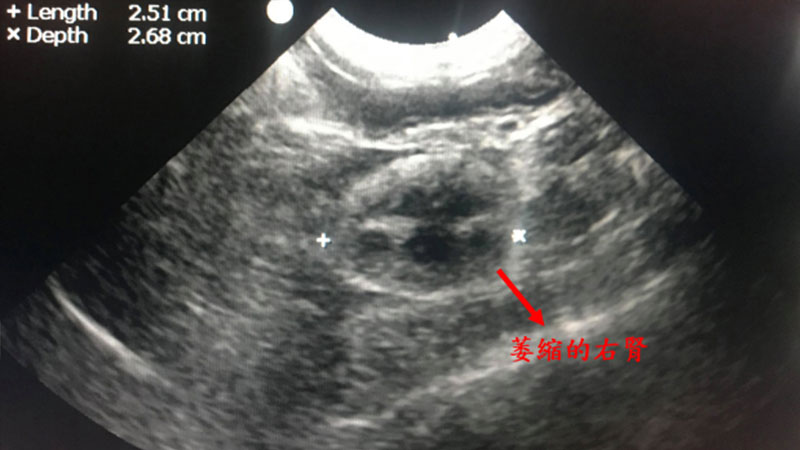

觀觀是一隻十歲齡、已絕育之雄性短毛家貓。就診的四天前在他院檢查出左後肢腫瘤、右腎萎縮,而後進行截肢手術。來本院主訴為術後陸續出現發燒、連續嘔吐、精神食慾下降、癱軟無力之症狀。

血液抹片呈現不再生性貧血,尿液檢查呈現低比重尿1.007(正常貓咪應在1.030以上),超音波顯示腹腔無明顯出血,但左腎萎縮、右腎輸尿管擴張最終診斷貓咪為急性腎損傷、貧血。